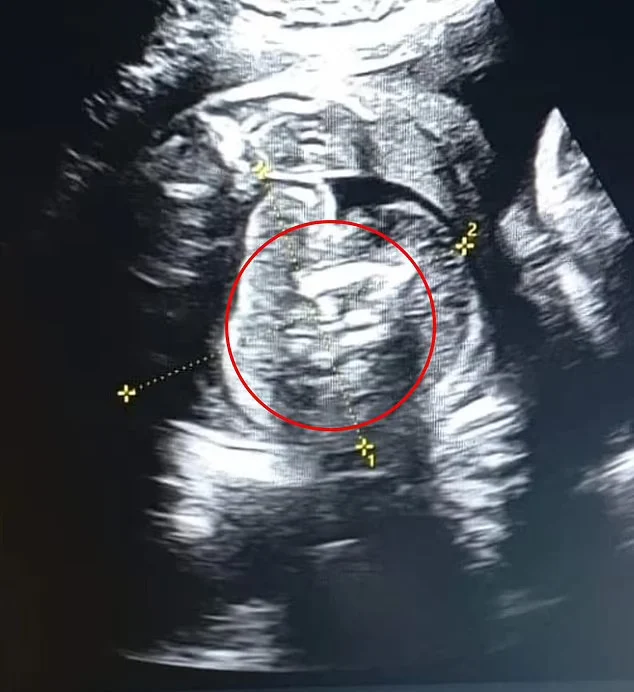

Αν και οι προηγούμενοι υπέρηχοί της ήταν φυσιολογικοί, οι γιατροί εντόπισαν «μία επιπλέον δομή που περιείχε οστά» στην κοιλιά του αγέννητου αγοριού της. Στη συνέχεια, η περαιτέρω εξέταση αποκάλυψε δύο εμβρυϊκές μορφές μέσα στην κοιλιά του μωρού.

Το φαινόμενο, που ονομάζεται «έμβρυο εντός εμβρύου» (Fetus in Fetu/FIF), είναι εξαιρετικά σπάνιο και έχει καταγραφεί μόλις 200 φορές στη ιατρική βιβλιογραφία, αναφέρει η Daily Mail, με εκτιμώμενη συχνότητα 1 στις 500.000 γεννήσεις.

Δεν είναι σαφές πόσες από αυτές τις 200 περιπτώσεις περιλάμβαναν πολλαπλά έμβρυα. Η γυναίκα γέννησε το μωρό της στις 1 Φεβρουαρίου, ενώ ήταν περίπου 35 εβδομάδων, και οι γιατροί αφαίρεσαν τα δύο έμβρυα από το στομάχι του μωρού, τα οποία είχαν σταματήσει να αναπτύσσονται σε κάποιο σημείο της εγκυμοσύνης.

Ο γιατρός Prasad Agarwal, ο οποίος πραγματοποίησε τον υπέρηχο, δήλωσε: «Ήμουν τυχερός για να παρατηρήσω κάτι εξαιρετικά ασυνήθιστο με αυτό το μωρό, ένα φυσιολογικά αναπτυσσόμενο έμβρυο με μερικά οστά και μια δομή που έμοιαζε με έμβρυο στην κοιλιά του».

«Σκέφτηκα ότι αυτό δεν είναι φυσιολογικό. Ήταν μια περίπτωση “έμβρυο εντός εμβρύου”, μία από τις σπανιότερες περιπτώσεις στον κόσμο», πρόσθεσε.